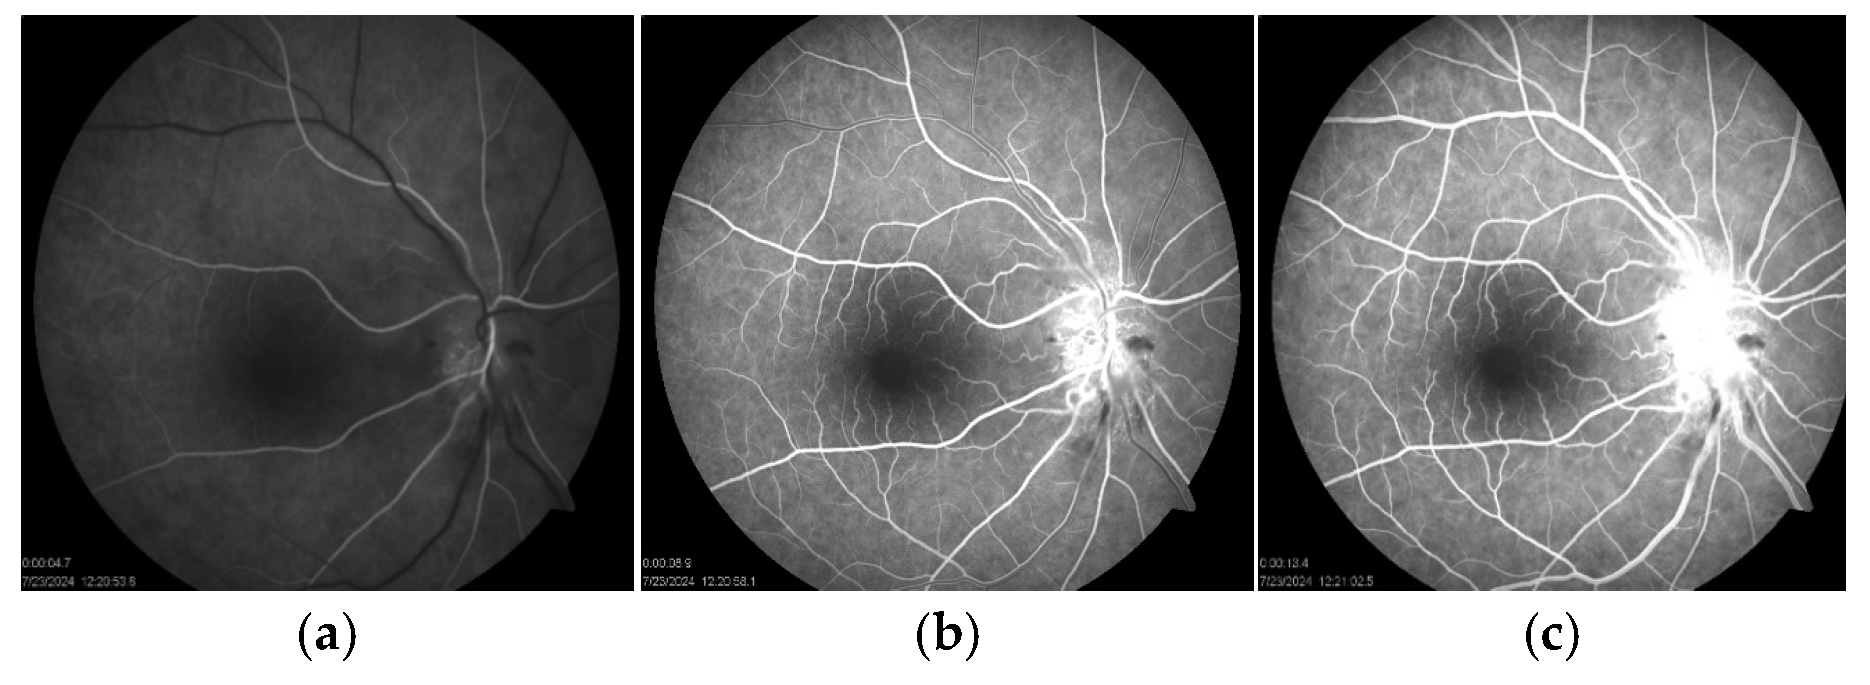

At that time, BCVA had decreased to 20/40, while the left eye remained at 20/20. Examination showed a positive relative afferent pupillary defect and an abnormal Ishihara test in the right eye. A fundus examination showed an optic disc edema with flame-shaped hemorrhages and cotton-wool spots in the peripapillary region (

Figure 1b). Fluorescein angiography (FAG) of the right eye demonstrated hyperfluorescence of the optic disc in the late phase, indicative of leakage from dilated peripapillary capillaries and impaired microcirculation (

Figure 5a–c).